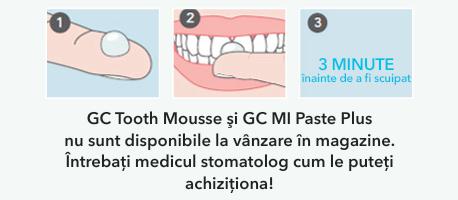

- Creme dentare cu RECALDENT™: Produse precum GC Tooth Mousse și GC MI Paste Plus conțin un complex derivat din proteina din lapte (cazeină), numit RECALDENT™, care livrează ionii de calciu și fosfat direct pe suprafața dintelui, ajutând la „reîncărcarea” smalțului slăbit.

- Mod de utilizare: Acestea nu sunt paste de dinți. Se aplică o cantitate mică pe dinți cu degetul sau cu un bețișor cu vată, după periajul de seară, și se lasă să acționeze, ideal peste noapte.

- Atenționări importante: Aceste produse se obțin doar la recomandarea și prin intermediul medicului stomatolog. Ele nu pot fi utilizate de către copiii cu alergie confirmată la proteinele din lapte. Acest aspect subliniază de ce parteneriatul cu medicul este esențial; el nu este doar un „reparator” de carii, ci și ghidul dumneavoastră către cele mai avansate și sigure metode de prevenție.